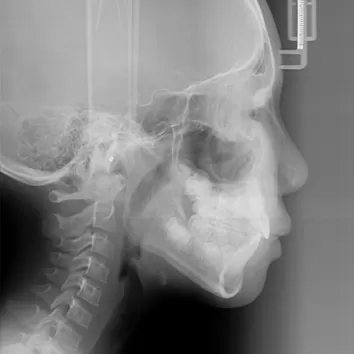

Rayons X avant le traitement

[Radiographie panoramique/Céphalogramme latéral]